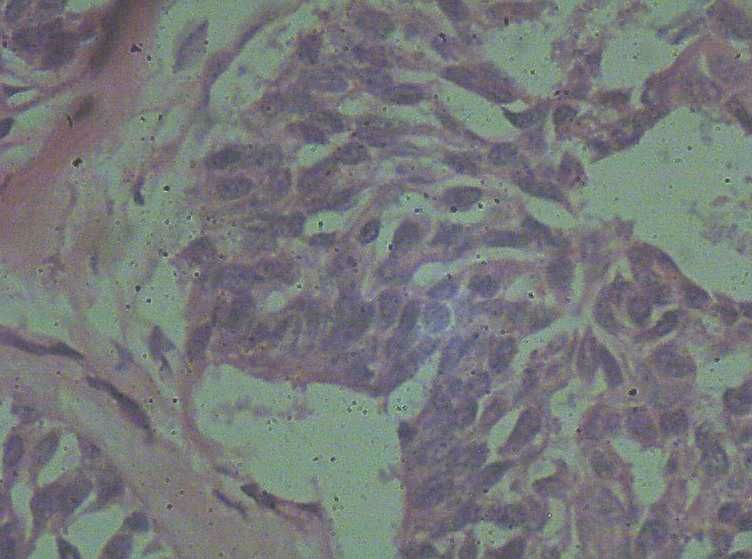

B3774乳腺积乳性包块?

女41岁,左腺包块。肉眼:不整形囊壁样组织,大小2*1.6*0.3CM,壁厚0.1—0.3,未触及结节,未见出血及坏死。

标签:乳腺纤维囊性增生症

似乎有导管扩张、慢性炎细胞浸润、大汗腺化生、普通型导管增生等病变,没有看到囊壁内衬上皮或囊壁结构。